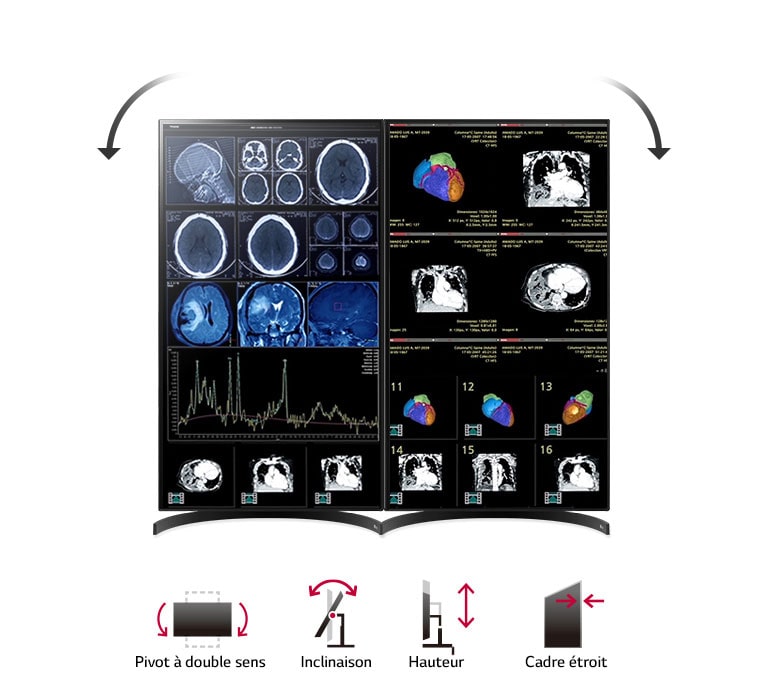

- Conception ergonomique

Ajustements de la position de l’écran

Inclinaison/hauteur/pivotement